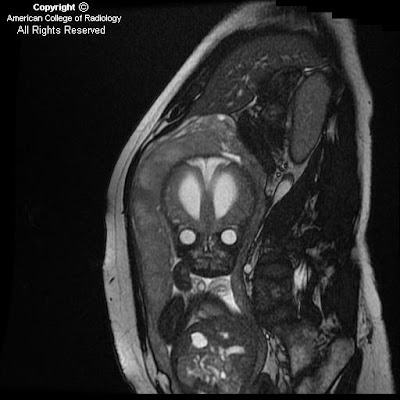

Fetal hydrocephalus

Findings

The cerebellar hemispheres (Figure 1), vermis and cisterna magna (Figure 1) are normal.

There is hydrocephalus, manifested by the marked dilatation of lateral ventricles, a midline falx (Figure 2 and Figure 3), and thinning of the cerebral cortical mantle (Figure 2 and Figure 3).

The fourth ventricle (Figure 4) is normal, therefore, the obstruction is suspected to be at the level of the Acqueduct of Sylvius (Figure 4). No obstructing lesions are identified.

Aqueductal Stenosis is more common in males as seen in this case (Figure 5)